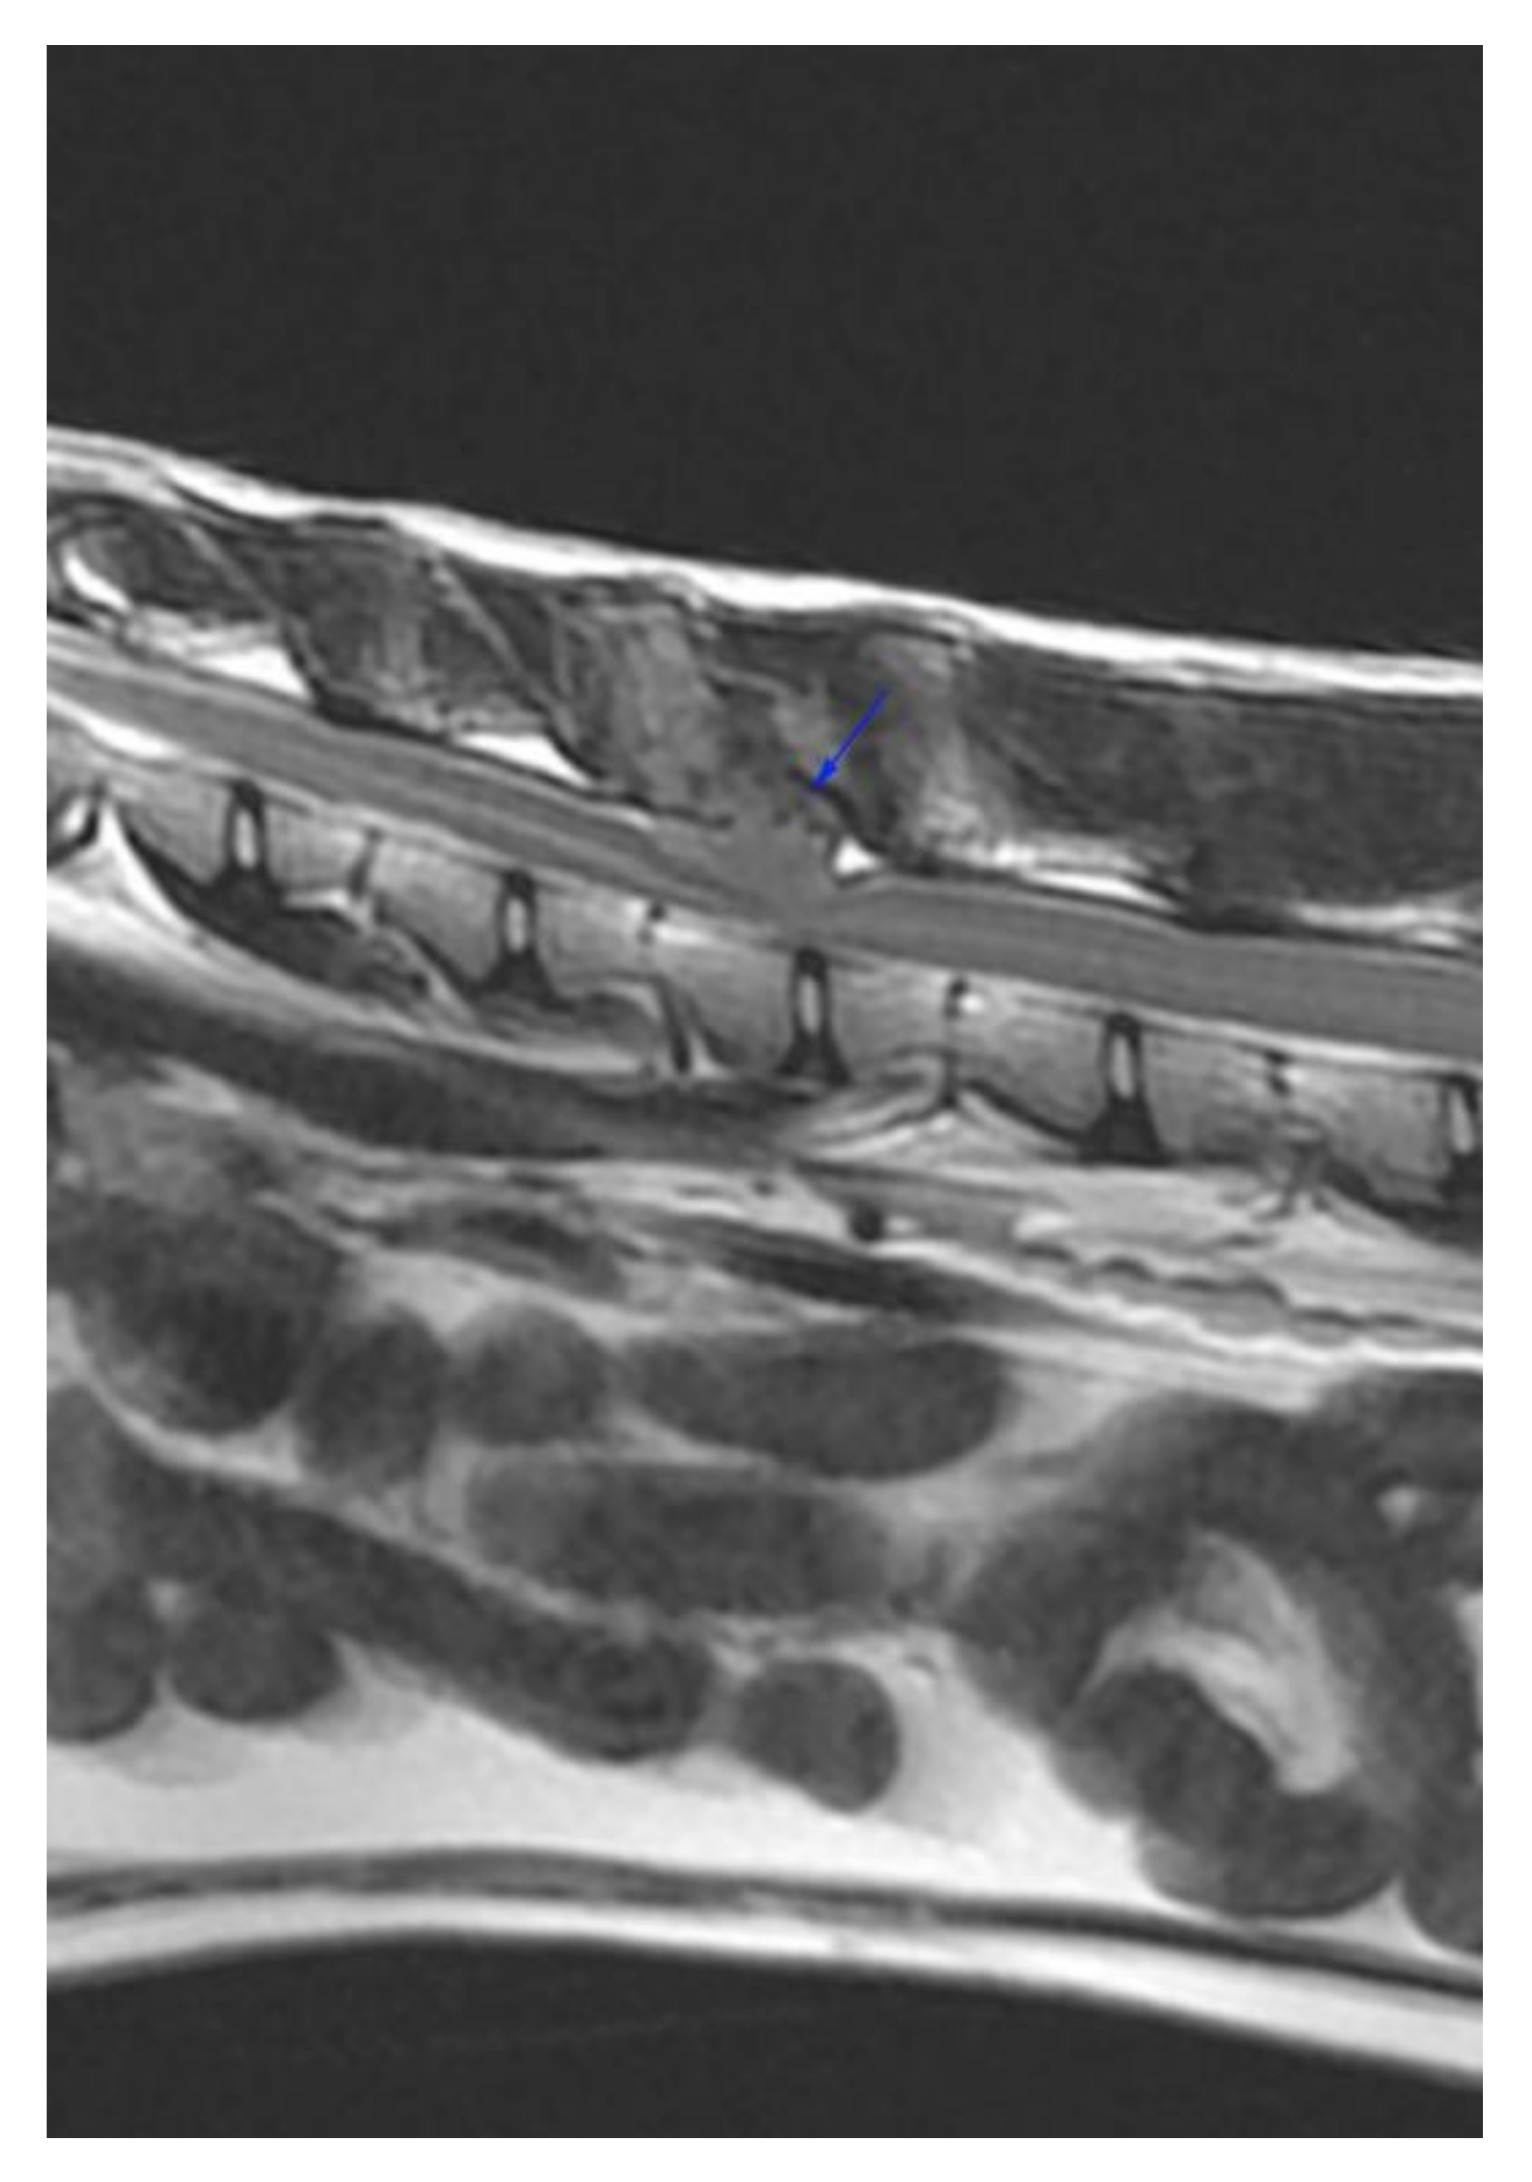

:1. Case Description

2. Materials and Methods

3. Results